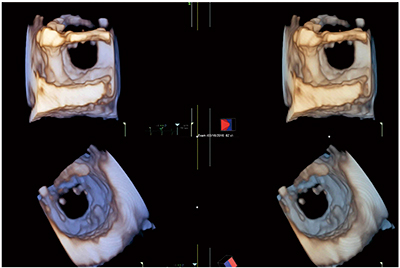

図4は三尖弁逆流が認められた症例の3D zoomの3D画像で,右房から見た三尖弁(図4 a)と,右室から見た三尖弁(図4 b)である。中隔尖,前尖,後尖を確認できる。ただし,症例によっては3枚の弁の同定が困難なこともある。

図4 三尖弁逆流が認められた症例の3D zoomの3D画像